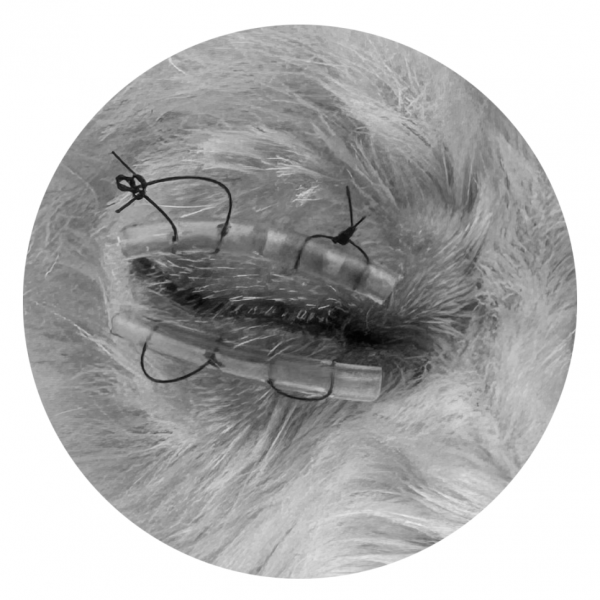

응급 수술 과정

→ 돌출된 안구를 정상 위치로 환납

→ 재탈구 방지를 위해 안검봉합술 진행

특히 강아지의 경우,

안구돌출 시 medial rectus muscle 손상에 의한 외사시가 흔하기 때문에,

안구 안정화를 위해 안검봉합술을 진행하였습니다.

이후 약 2주간 치료를 진행했고, 회복 후 봉합은 제거했습니다.